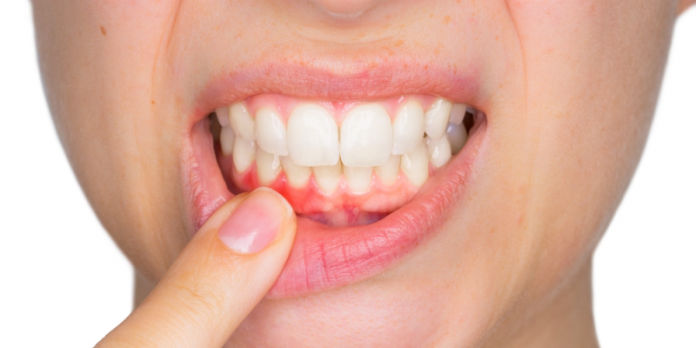

Recessão gengival é uma condição bastante comum entre pacientes de ambos os sexos e em diferentes idades, aumentando sua frequência com o passar dos anos. As maiores queixas dos pacientes com recessão gengival são hipersensibilidade radicular e aspecto antiestético.

Para isto, existem diversos tratamentos, sendo as cirurgias de enxerto para recobrimento radicular as mais utilizadas.

A cobertura total das raízes por tecidos gengivais espessos e saudáveis é indispensável para eliminar esses sintomas severos. No entanto, é de grande importância o conhecimento de suas técnicas, indicações e contraindicações, a partir das considerações anatômicas de cada caso.